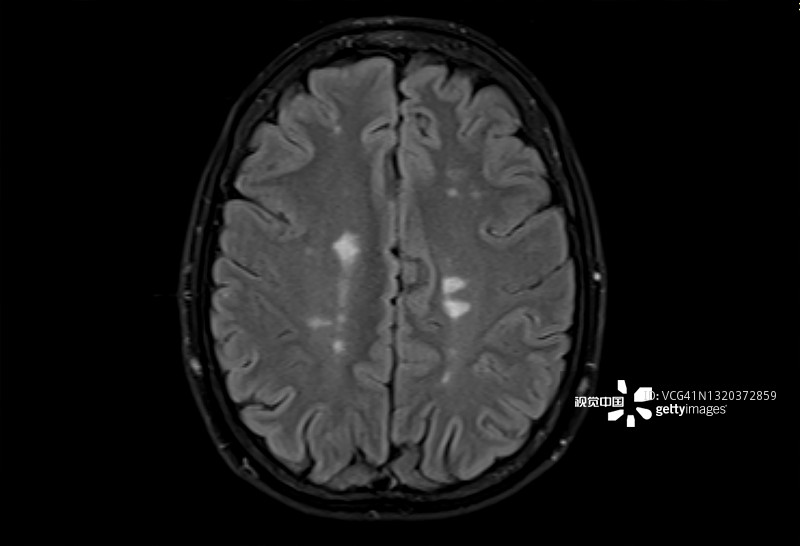

多發性硬化癥 (MS):MS是一種中樞神經系統 (CNS) 的慢性自身免疫和炎癥性疾病。MS與免疫系統介導的自身反應性T細胞和B細胞對神經元髓鞘的攻擊有關,導致脫髓鞘并最終導致神經元丟失。由于中樞神經系統中神經變性和斑塊的形成,MS患者會根據斑塊的位置經歷特定的神經功能障礙。例如,視神經中的斑塊會導致視力喪失。